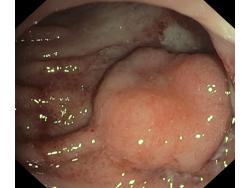

Nowotwory przewodu pokarmowego